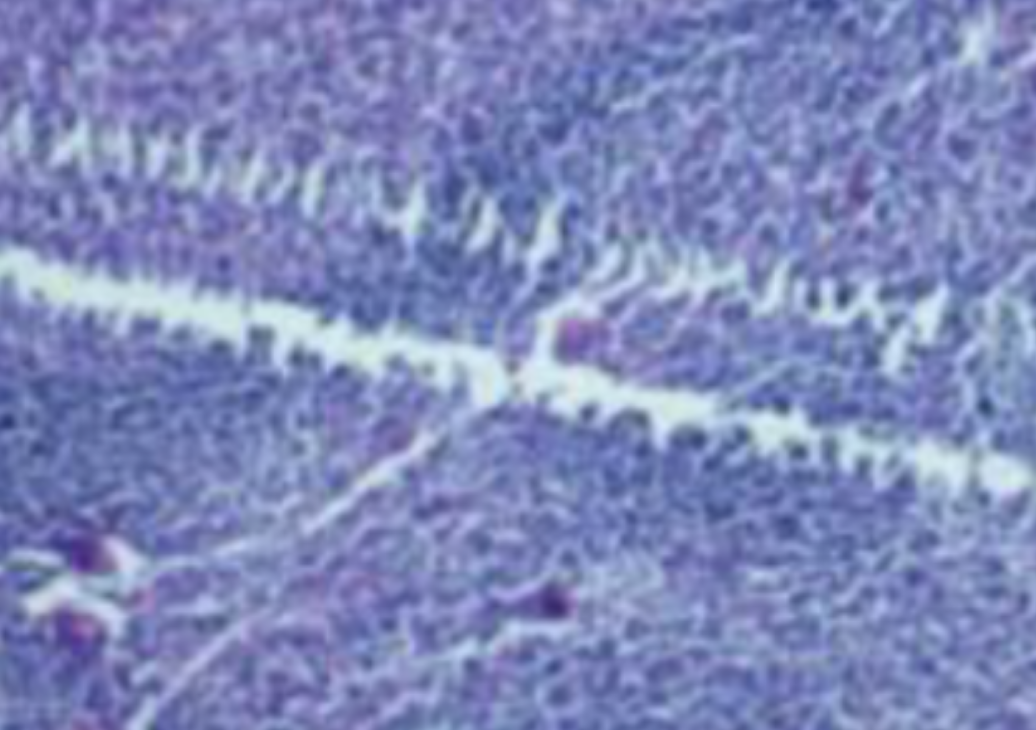

形成原因:切片经梯度乙醇处理后没有完全脱水,导致二甲苯透明、中性树胶封固后残留大量水分。 解决方法:首先移去盖玻片,用二甲苯溶解封固剂如中性树胶,再将切片置入无水乙醇内,待切片重新脱水完全后,用二甲苯透明处理,中性树胶封固。要注意所有用于脱水和透明的液体,在使用一定时间后,应及时更换。 二、细胞核呈红、棕色 形成原因:苏木精染色液过度氧化,切片在苏木精染液染色后返蓝不足。 解决方法:每次染色之前检查苏木精染色液的染色能力,发现苏木精染色液氧化过度应及时更换。此外,切片经苏木精染色后,要给切片以足够的蓝化时间,蓝化过程可用流水、温水、弱碱性溶液(如稀氨水或0.2%碳酸氢钠)等处理。 三、切片在脱蜡后出现大片白色斑点 形成原因:由于烤(烘)片温度太低,切片上的组织蜡膜在脱蜡前没有充分烤(烘)融化。或是因为切片在二甲苯液中停留时间不足,或二甲苯使用过久,造成的脱蜡不彻底。 解决方法:若是由于切片烤(烘)温度低所致,可以先用二甲苯去除切片上的封固胶,然后重新用二甲苯脱去切片上的石蜡,再进行后续染色。若是由于切片在脱蜡的二甲苯中停留时间不足或脱蜡二甲苯使用过久浓度不足所致,则需将切片退回到二甲苯中,停留较长时间,或更换二甲苯液体重新脱蜡,再入乙醇重新脱二甲苯,入0.5%盐酸水溶液褪色后,重新HE染色。 四、细胞核苍白暗淡,即苏木精染色太淡 形成原因:切片在苏木精染色液停留时间太短;苏木精染色液过度氧化,失去染色能力,不能再继续使用;分化步骤处理时间过长;固定不及时。此外值得注意的是,若骨组织细胞核暗淡,大多是脱钙过度造成的。 解决方法:切片重新染色。如果组织在酸性固定液(如Zenker、Bouin)或非中性缓冲甲醛液固定时间过长,细胞核染色能力将减弱,需增加其在苏木精染色液的时间,或用一些方法增加组织的嗜碱性,以改善细胞核的着色。例如,上述组织玻片可以使用Weigert铁苏木精染色液。如果组织是用Zenker液固定的,可将切片脱蜡后放在5%碳酸氢钠溶液3~4h,流水冲洗5min后染色。如果组织是用Bouin液固定的,可将切片脱蜡后放在5%碳酸锂1h,流水冲洗10min后染色。 五、细胞核过染,苏木精染液占据了细胞质 形成原因:玻片在苏木精染色液停留时间过长,或是切片太厚、分化步骤时间太短。 解决方法:如果不是因为切片太厚(用显微镜仔细上下微调,只有一二层细胞核层次),就需将切片进行脱色、漂白、重新染色,适当调整染色和分化时间。但如果确定是由于切片太厚导致的细胞核过染,则需要重新切片。 六、伊红着色淡 形成原因:可能是伊红染液pH值大于5,也可能是蓝化液残留过多,切片太薄,或是切片经伊红染色后在乙醇脱水时间过长。 解决方法:检查伊红染液pH值,必要的话,用乙酸将其调节在4.6~5.0之间,从而使伊红染色色彩艳丽。此外,确保每次蓝化步骤完成后,使用的弱碱性溶液被充分洗去,玻片上没有残留的弱碱性溶液。最后,检查切片的厚度,且脱水时不要让切片在低浓度乙醇中停留时间过长,因为含水多的低浓度乙醇会将切片伊红的颜色分化掉。 七、细胞质过染、分色不足 形成原因:伊红染色液浓度太高,特别是存在焰红燃料、四溴四氯荧光素钠。切片在伊红染色时间过长,或是切片在伊红染色后经乙醇脱水步骤时时间太短,而使乙醇分化伊红的作用不能产生,都能够使细胞质过染。 解决方法:适当稀释伊红染色液,减少伊红染色时间,或使切片在乙醇脱水等步骤时,停留时间相对均匀。同样,也要检查切片的厚度是否合适。 八、切片中出现蓝黑色沉淀物 形成原因:苏木精染色液中的金属膜黏附在玻片上。 解决方法:染色前仔细过滤苏木精染色液,建议使用半氧化苏木精染色液,如Gill苏木精染色液,可以避免过多的金属膜产生。 九、光镜下切片某些区域难以聚焦 形成原因:盖玻片上可能有封固切片的封固剂。 解决方法:移去盖玻片,重新用干净的盖玻片封片。检查切片封片方法,是人工手工封法,还是机器自动封法,如有问题及时调整。 十、封固剂从盖玻片与载玻片之间的缝隙回缩 形成原因:盖玻片弯曲或不平整,或是封固剂含二甲苯过多,稀释过度。 解决方法:移去盖玻片,重新找一张盖玻片,用干净的封固剂封片。如用手工封片法,保证在封固结束时,封固剂容器盖子为紧闭状态。且尽量使用小的容器盛装封固剂,一旦封固剂太黏稠,就可以选择废弃。 十一、细胞核呈灰蓝状态 形成原因:可能由于组织处理温度过高、过热,在液体石蜡中停留的时间过长。或是固定时间太短后,直接在高浓度的乙醇中进行了脱水处理。 解决方法:理论上来说,仅在组织浸蜡步骤才进行加热,组织不能在热蜡液中停留太久。如果由于某些原因不能进行下一步包埋处理,可将组织连同塑料包埋盒一并放置在室温空气中,冷却凝固,以备包埋。待需要包埋时再重新加温直至石蜡融化即可。组织在处理前必须确保固定良好,脱水最好能从低浓度的乙醇开始。 十二、类色素的点状结晶和黑色光滑细胞核 形成原因:这种裸核改变是因为切片封片前放置在空气中的时间太长,以至于二甲苯挥发,切片干燥。 解决方法:移去组织切片上的盖玻片和封固剂,重新处理。将切片水洗数分钟,然后重新脱水、透明、封固。封片过程中要保持组织切片的轻度湿润,尽量不要让其干燥。 十三、染色过淡或过浓 解决方法:如果染色过淡,可以增加染色剂的浓度、延长染色时间或更换新鲜的染色剂;如果染色过浓,则应减少染色剂的浓度或缩短染色时间。 十四、切片出现叠加褶皱 形成原因:新购买的玻片洁净度不够、用镊子撑开切片时操作不够熟练未能平整伸展,或玻片表面有油脂,切片粘贴不牢。另外,烤片时间不足、烤片温度过低或切片过厚造成切片脱落,都会造成重叠或有皱褶的情况。 解决方法:新购买的玻片最好能用硫酸清洁液浸泡一晚,然后流水冲洗干净。在适宜的温度下烤片时间宁长勿短,保证有充足的烤片时间和温度。另外,切片刀要锋利,才能切出厚薄适宜的切片,保证切片不会因为过厚而脱落。 十五、组织残缺不全或有刮划痕迹 形成原因:组织残缺不全是由于切片时修整蜡块时深度不够、组织没有全部暴露于切面。切片的刮划痕迹是由于切片刀的刀锋有缺口、包埋的组织有异物,或是钙化组织、骨组织及包埋石蜡有沙粒造成的。 解决方法:修整蜡块时保证组织块全部暴露于切面,切片时保证切片刀的锋利没刀口。同时在组织取材时去除手术异物和钙化组织。最后,骨组织要完全脱钙,这样可以保证切片的完整和平整美观。 *注:由于实验中导致结果出现误差的原因多种多样,以上内容仅供参考,具体根据实际情况进行判断。